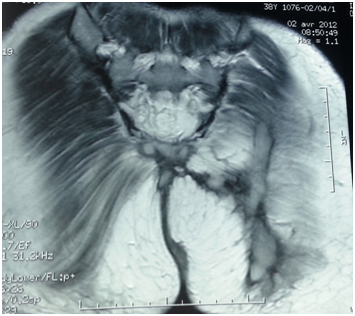

A patient, aged of 43 years old, without any particular previous pathologies, was admitted for the exploration of chronic suppuration of the perianal and gluteal region which has been in progress since 10years without any troubles of transit or signs of tuberculosis impregnations. The patient was operated, one year ago, for anal abscess. But she had noted a quick recidivism of the suppuration and a multiplication of the external orifices of the fistulas. The examination of the anal margin had revealed 4 productive orifices surrounded by a sclerotic and carded skin. The hemoglobin level was 9g per dl (microcytic hypochromic anemia) and there was an inflammatory syndrome. The serology HIV was negative. Rectoscopy revealed two internal orifices of the fistula. The ileocoloscopy was normal. The thoraco-abdominal scanner was normal. The pelvic MRI revealed extra-sphincterial multiple anal fistulas (Figure 1). Tuberculin intradermal reaction was positive at 15mm. The anatomopathological examination of the skin biopsies of the gluteal region had lead to a granulomatous dermatitis of the anal region without caseous necrosis. The direct bacteriological examination as well as the BK PCR of these biopsies was negative. One month after these samples were taken, Lowenstein Jensen culture of these biopsies and stools showed the presence of BK, which is sensitive to the usual anti-tuberculosis drugs. The patient was treated with Quadratherapy (rifampycin-isoniazid-ethambutol-pyrazinamide) for 2months followed by 4 months of dual therapy (Rifampycin isoniazid). The outcome was favorable with drying of the fistulas and disappearance of the inflammatory syndrome as early as 30day of treatment (Figure 2) without recurrence after discontinuation of the treatment with a current follow-up of 4,5years.

Figure 1 Pelvic MRI revealed extra-sphincterial anal fistula.